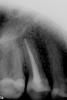

Ashley Опубликовано 11 мая, 2010 Автор Поделиться Опубликовано 11 мая, 2010 А это снимок зуба, сделанный вчера, когда я снова обратилась к врачу с вопросом о причине боли. Ссылка на комментарий

x3m Опубликовано 11 мая, 2010 Поделиться Опубликовано 11 мая, 2010 Каналы были прочищены, в зуб был вставлен штифт из титана. Зуб был сточен очень сильно, на него налеплена светоотверждающая пломба. нужна коронка и ВКВ, а не анкер и фотополимер. ...в зубе начались ноющие боли, боль отдает в ухо, ноет даже ночью. т.к. есть второй канал. Это хорошо видно на контрольном (вчерашнем) снимке.Оценить, как установлен штифт - невозможно. Его не видно на снимке.Анкера хорошо достаются. Главное, чтобы доктор умел это делать и имел ультразвуковой наконечник. зы. а что по прошествии восьми лет с зубом будет? о прогнозах спросили? Ссылка на комментарий

x3m Опубликовано 12 мая, 2010 Поделиться Опубликовано 12 мая, 2010 Я бы не был столь категоричен. Во-первых не все врачи являются приверженцами вкладок, и нет стандарта, в котором было бы написано "на депульпированный пятый обязательно вкладку и коронку". эммм... я так... думаю. (с)"Мимино" ессно, нету стандартов, что на депульпированный пятый надо обязательно ВКВ и коронку. НО. на контрольном снимке (после пломбировки каналов с пучком гутты) есть все показания для ВКВ и коронки, а не для анкера с лепкой композитом... или нет? в этом случае вопрос не в религии и склонности докторов к анкерам/ВКВ. А в присутствии отсутствия достаточного массива твердых тканей. Что есть клиническим показанием для вышеизложенной техники восстановления. а к качеству пломбировки одного канала претензий нет. все хорошо. по поводу второго канала - я его увидел вот здесь:http://i061.radikal.ru/1005/e5/7c7363b88f90.jpghttp://s006.radikal.ru/i213/1005/79/997e7c291cb1.jpg периодонтальная щель второго корня и отдельный апекс имеютЦа. Поиграться бы с ангуляцией - избежали бы наложения. Ashley, попросите врача поменять угол рентгенсъемки, "сфоткать" зуб под другим углом. Ссылка на комментарий

x3m Опубликовано 12 мая, 2010 Поделиться Опубликовано 12 мая, 2010 Я бы с вами поговорил об этом, но не в этом разделе....Ну и согласитесь, обострение после пломбирования, не такая уж редкая вещь.о показаниях? давайте поговорим.Обострения бывают, согласен... Но пульпитообразная симптоматика - очень уж напрягает. Ну не похоже это на периапикальные реакции, верно? И через 2 недели после пломбировки...А если есть остаточные симптомы от нераскопанных каналов плюс рентгенподтверждение - их надо раскапывать вне зависимостей от уровня ответвления. Ссылка на комментарий

x3m Опубликовано 12 мая, 2010 Поделиться Опубликовано 12 мая, 2010 (изменено) ...а будет мучить своего врача. Я предлагаю другой вариант - сделать снимок через пол-года, там то уж точно будет видно, всё в порядке или нет.З.Ы. Конечно если боль усиливается, то однозначно распломбировывать, тогда ваше предположение будет правильным.что это - раздвоенная верхушка (очень уж рано она раздвоЯется) или второй канал - можно выяснить сейчас, а не через полгода. как - мы уже озвучили.да и что через полгода увидит врач, если вторая "веточка" все же есть? минус-кость? В любом случае щечный апекс требует участия.я все-таки предлагаю такой вариант: сейчас, не дожидаясь особо ничего, сделать несколько прицелов в разных проекциях. И только тогда ставить на диспансер (по другим соображениям, не буду в пациентской)или лечить.зы. Ashley, не мучайте своего врача, не надо Изменено 12 мая, 2010 пользователем x3m Ссылка на комментарий